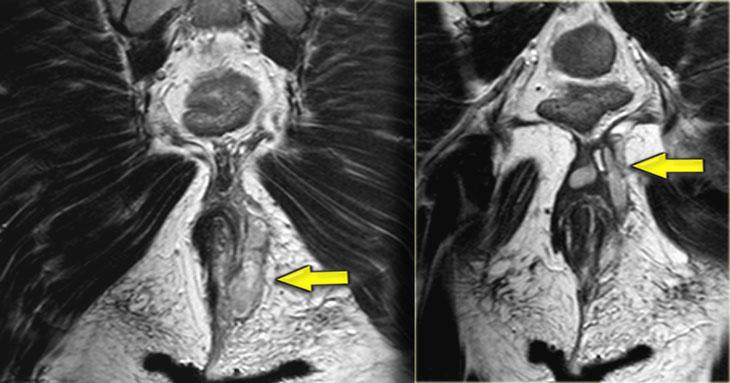

Bên trái là hình ảnh một bệnh nhân có rò quanh hậu môn trong bối cảnh bệnh Crohn.

Tiếp tục xem hình ảnh coronal.

Trên hình ảnh coronal, hình ảnh dày thành ruột được ghi nhận rõ ràng.

Hình ảnh cắt ngang xóa mỡ cho thấy tình trạng viêm xuyên thành với sự thâm nhiễm vào lớp mỡ mạc treo.